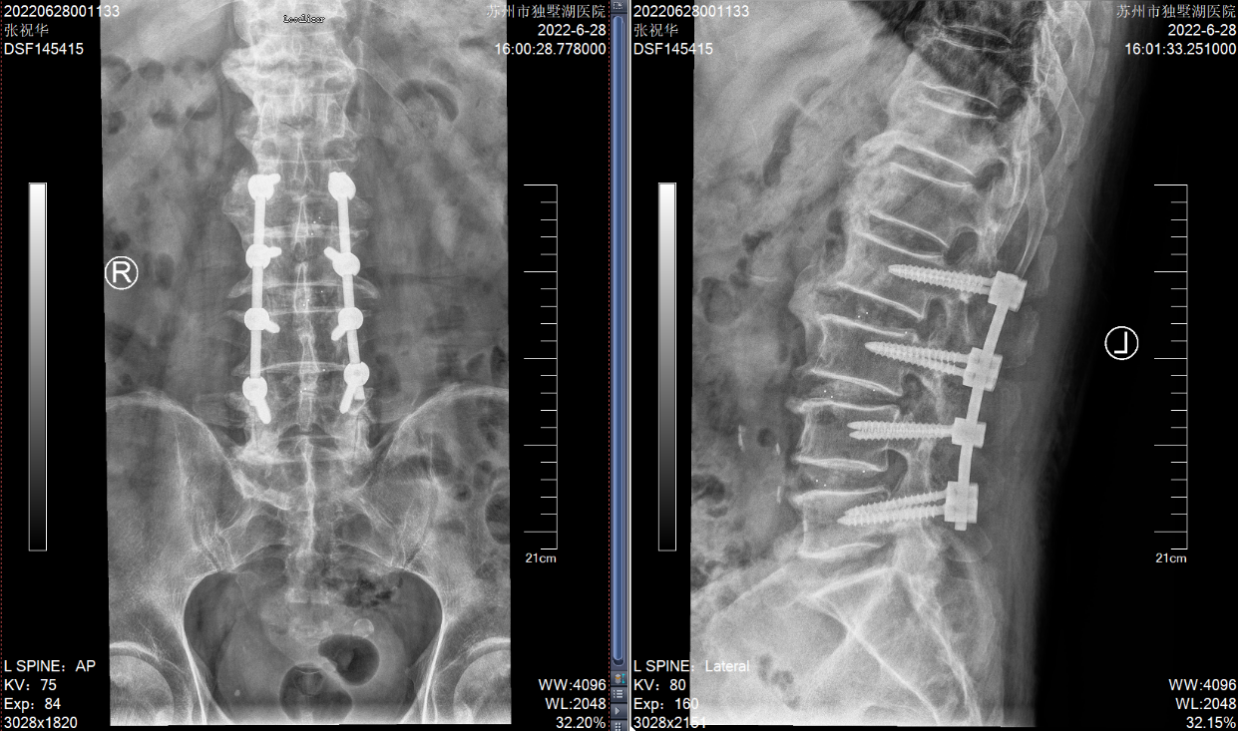

张老爷子今年84岁高龄了,家住盐城建湖。之前老人家身子骨一直硬朗,吃得好,睡得香,直到近年腰腿痛再次发作,如今已经发展到了几乎寸步难行的程度。说起来,这位老爷子算是姜主任的“老熟人”了,二十多年前他就曾因“腰椎间盘突出症”在苏州接受过姜主任的手术,术后恢复良好。但近几年,随着年龄增长,老爷子的腰椎疾患又犯了,且加重很快。这次在他两个儿子的陪同下,特地从外地赶来独墅湖医院,希望姜主任能给他解决病痛。姜主任仔细检查后发现:老先生腰椎退变严重,患的是一种名叫“腰椎管狭窄症”的疾病。表现为“腰腿痛”和“间歇性跛行”的症状,需要做彻底的“椎管扩大减压+椎弓根螺钉内固定+椎间融合术”。刚讨论完老先生的病情,患者的小儿子说:“给我哥看看吧,他也挂了您的号,是颈椎病,可能也要手术。”姜主任分析过病情后确认患者得了一种称为“后纵韧带骨化症”的颈椎病,几年前就已确诊,因为害怕手术不成功会导致瘫痪,一直拖到现在,已经严重到难以独立行走。这次下定决心与老父亲一起来苏州接受手术。由于床位紧张,老先生首先住进医院接受了手术。手术很顺利,术后仅仅两天,他已经可以下床活动,双下肢症状明显缓解。

(腰椎MRI提示L2-5椎间盘突出,椎管狭窄明显)

(术后复查腰椎X片:此次对患者进行了L2-5的椎管扩大减压+神经根松解+椎弓根螺钉固定+椎间融合术)